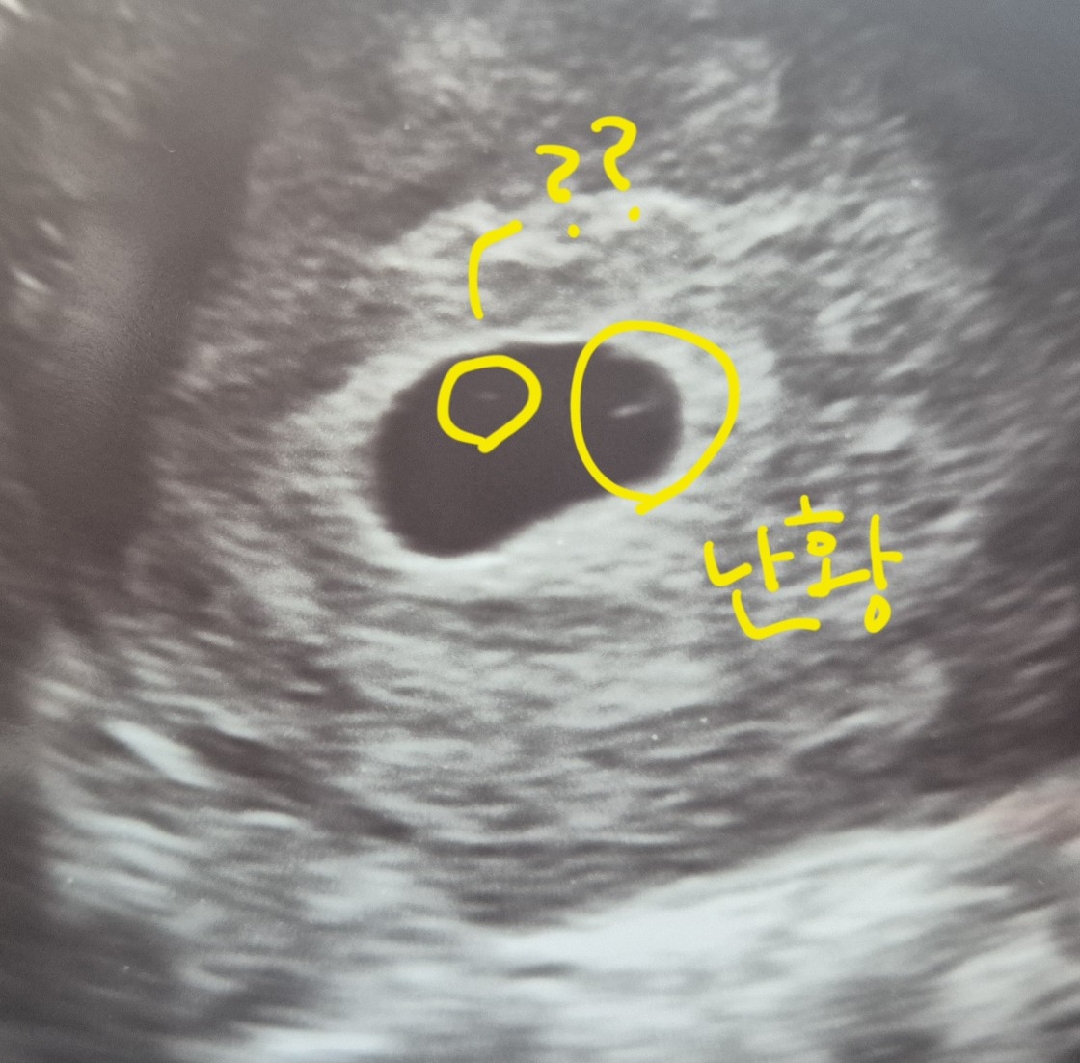

난황크기가 작아요

8.6 5주3일차 아기집 확인(메인병원) 8.11 6.1일차 난황 확인(서브병원) 난황크기가 아기집에 비해 많이 작은거 같은데 문제가 있는걸까요? 난황 옆 작은 점은 뭘까요?

크면 문제가 있다고 들었어요. 옆에도 난황아닌가요?